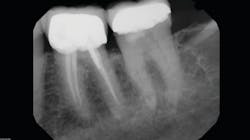

For those on the fence due to cost, there are 2-D upgradeable units. But with the declining costs of 3-D technology during the last 10 years, it’s debatable whether it’s worthwhile to postpone what will soon be mainstream. As I’ve often written, better to immerse oneself in the technology and become comfortable with what your competition already knows; 3-D is the present and the future. Those who wait to take the plunge risk being left behind. Look at the visual differences between 2-D and 3-D and tell me you don’t need this.